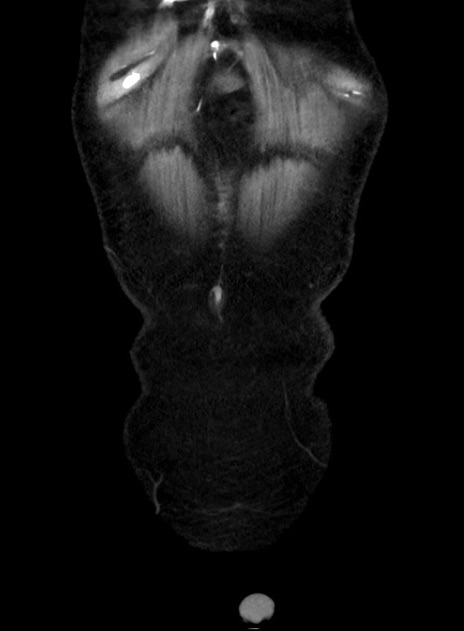

症例38(冠状断像)

【症例】70歳代 男性

【主訴】腹痛・嘔吐

【現病歴】昨晩より、嘔吐・腹痛あり。今朝になっても嘔吐あり。来院。

【既往歴】心臓バイパス手術、開腹胆摘、腸閉塞

【身体所見】BP 107/71mmHg、HR 116/min、腹部:平坦、軟、下腹部に軽度圧痛あり。反跳痛なし。

【データ】WBC 15100、CRP 0.32